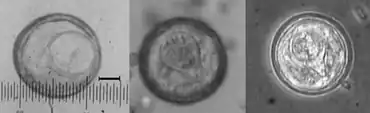

Like all Cyclophyllidea, Bertiella has a scolex, suckers, and many segments called proglottids. These are released into the body from the adult tapeworm, contain both male and female anatomical structures, and are in stages of mature, postmature and gravid. In general, human Bertiella morphology is not well understood due to the rarity of infection, and therefore limited possibility for study and observation. Particularly lacking are descriptions of adult stages of the species. Most common are studies of proglottids passed in stool samples of infected hosts. Studies have shown that specimens collected from humans are essentially morphologically the same as specimens collected from monkey hosts, except for some anatomical differences in reproductive organs. However, these discrepancies in morphological findings have led researchers to postulate that there may be more than two human Bertiella species, as previously believed. These gravid proglottids in stool are white and can measure around 11 mm for maximum length and 8 mm for maximum width. Full tapeworm observations in the past have included a worm that was 130 mm long, 15 mm in width, and 2.5 mm in thickness. It had a scolex, neck, and 418 proglottids.

Differences in human species: B. mucronata has smaller eggs than B. studeri. There are filaments arising from the pyriform apparatus clearly identifiable on B. studeri but not B. mucronata.

A Bertiella infection is typically diagnosed by observing eggs or proglottids in stool. They can be white, around 8 mm wide and 11 mm long, and moving. It can also be identified by presenting with common signs and symptoms in an area where disease is present, and there is close contact with soil and/or nonhuman primates. In many of these areas, other parasitic diseases can be a problem to the population, and finding the proglottids in stool samples can be the only way to distinguish Bertiella from other parasites. The appearance of the eggs has been described as "slightly oval and thin-shelled" while the "embryo is encased in a capsule or pyriform apparatus with two blunt horns."[1]